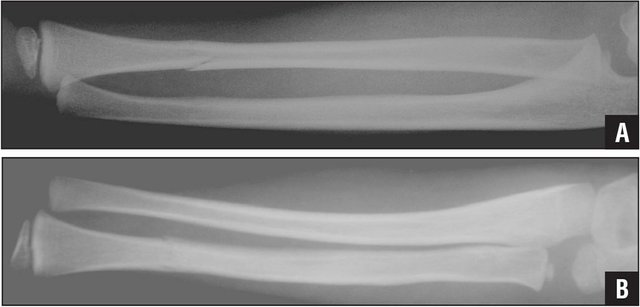

Bowing fracture

Again, generally seen in children, a bowing fracture is caused when a bone isn't so much brittle as malleable. As such when a force is applied the bone doesn't break like a stick of chalk but bends like a paperclip. Compare the top and bottom images below and note the clear bending of the bones in the lower image. For bonus points, can you spot the fracture in the top image?